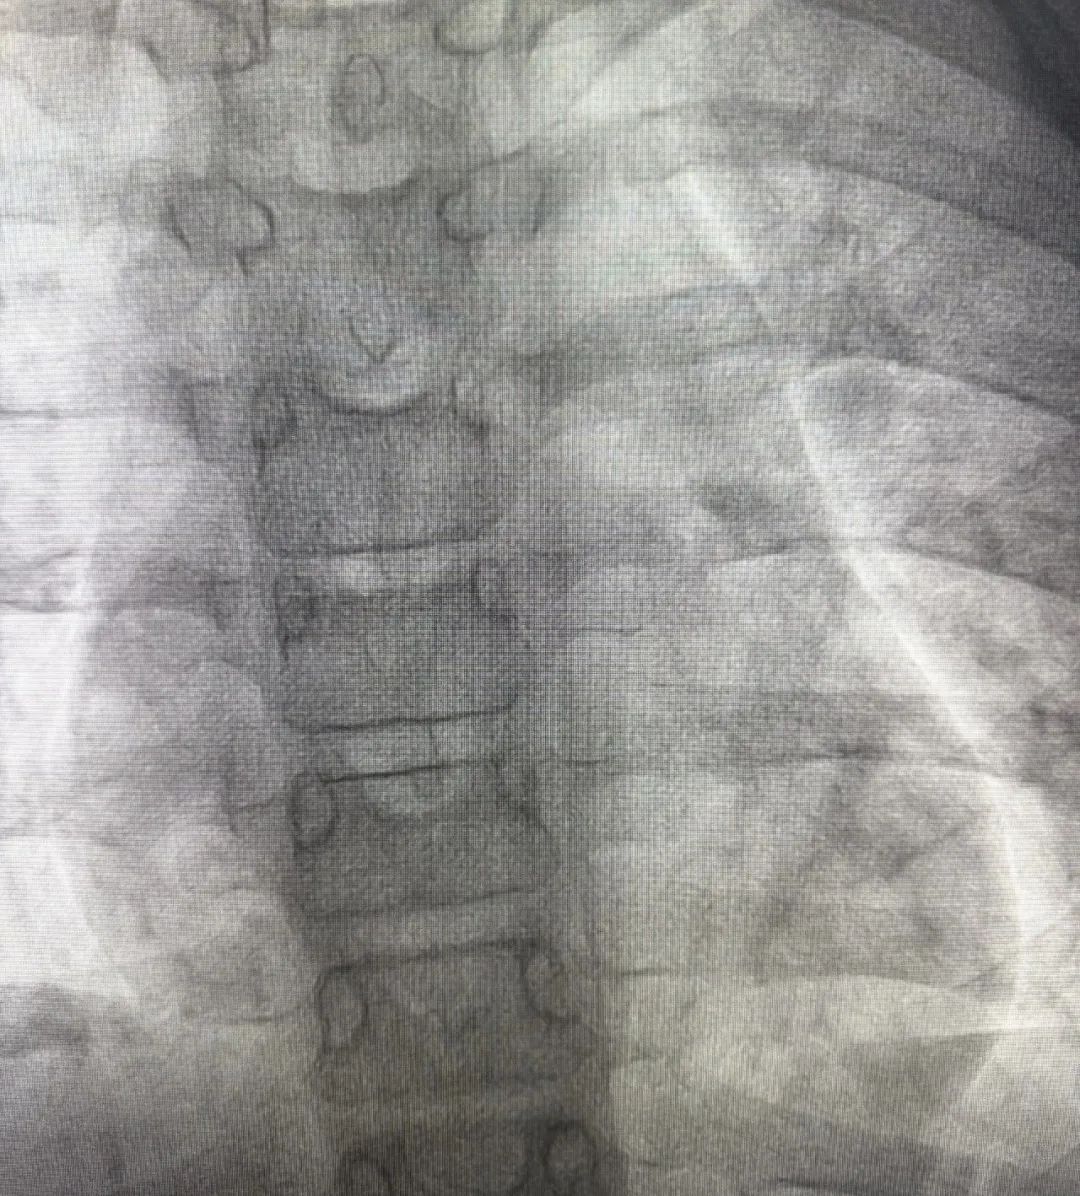

术前超声图

术中经股静脉穿刺顺利建立手术路径(股静脉-右心房-房间隔缺损-左心房)。随后,术者置入输送鞘管,并沿鞘管将MemoSorb可降解ASD封堵器精准送至心脏房间隔缺损处,严格遵循“一贴、二扣、三锁、四剪、五撤”的规范化“5S”操作法释放封堵器,先后展开封堵器左右盘面,牵拉成型线确保其成型稳定后,锁定封堵器,使之紧贴房间隔。确认封堵器形态良好、位置正确后释放封堵器,术后即刻超声显示无残余分流,肺动脉收缩压由术前的35mmHg降至28mmHg,左心功能正常,手术圆满成功!术后1天复查证实封堵效果理想。目前患儿恢复情况良好,已出院回家,回归正常学习生活。

术后即刻超声图

术后即刻超声图

术后即刻DSA图